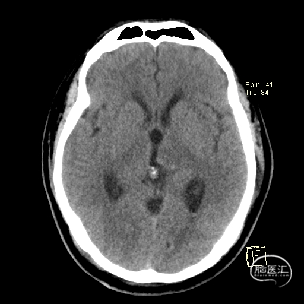

术后当天CT

术后1周CT复查